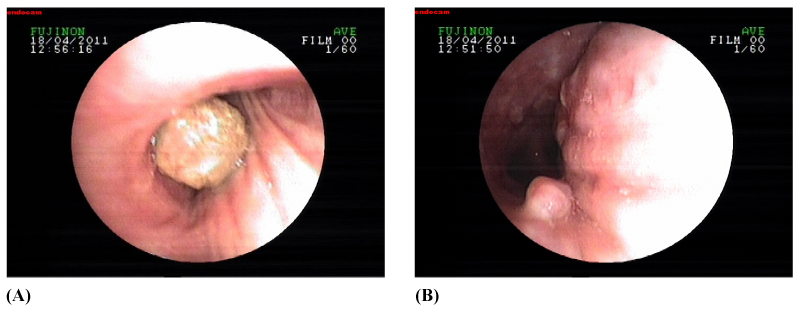

Blood tests done showed a mild leukocytosis (17300IU/mL); renal and hepatic panels were normal. Arterial blood gas analyses were also normal. His chest radiograph showed no abnormality, except a suspicious heterogenic density behind the left heart silhouette. CT scans of the thorax are shown below in Figure 1A and Figure 1B. Bronchoscopy was then performed, which showed a polyploidy lesion on the posterior wall of the left main bronchus, whereas an oval shaped mobile body was observed over the right main bronchus, under the right upper lobe division (Figure 2A) (Figure 2B). The pathological diagnosis of the specimen taken from the polypoid lesion was compatible with active chronic granulation.

Figure 2 A) Bronchoscopic images showing an oval shaped body in the right main bronchus, under the right upper lobe division. B) A polypoid lesion on the posterior wall of the left main bronchus.